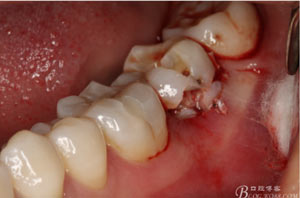

圖6.微創(chuàng)挺拔除37.

圖7.37牙冠碎裂。多生牙壓迫吸收程度嚴(yán)重。

圖8.拔除的37頰側(cè)的牙根完全被壓迫吸收完